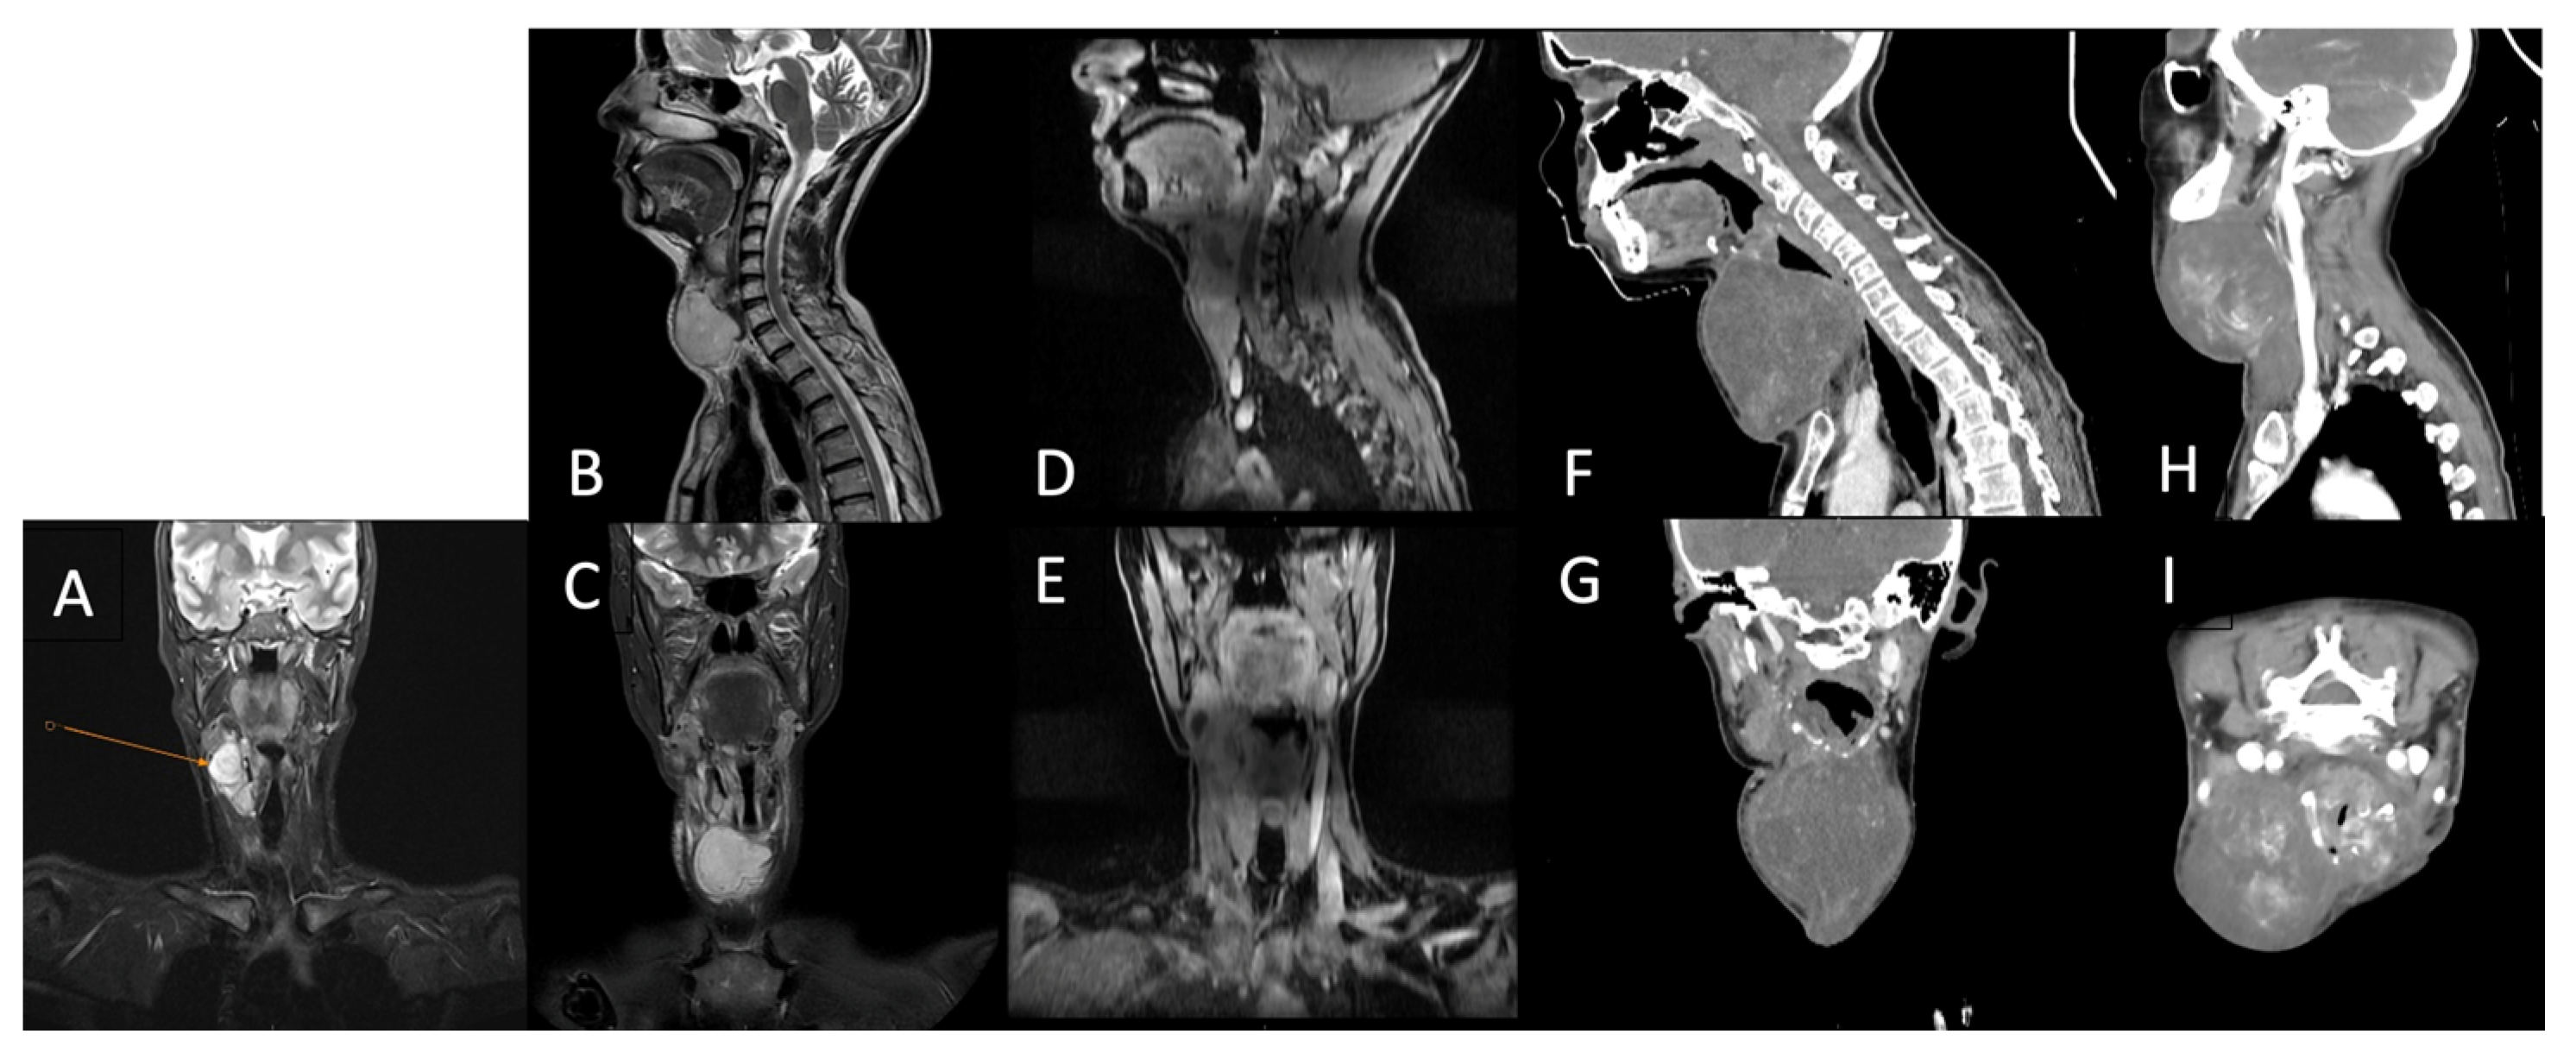

Postoperatively, the patient underwent adjuvant radiotherapy (total dose, 50 Gy in 25 fractions) to the left chest wall using a Halcyon linear accelerator, which was well-tolerated. Three months after radiotherapy, the patient developed dysphonia, and a subcutaneous tumor mass was observed in the right lateral cervical region. Cervical ultrasonography revealed immobile right lateral cervical lymphadenopathy measuring approximately 4 × 4 cm, with a normal-sized thyroid gland. Cervical magnetic resonance imaging (MRI) revealed a bilobed malignant tumor mass in the right laterocervical region, with invasion of the right thyroid cartilage and partial involvement of the right vocal cord. PET-CT showed metabolically active secondary lesions in the right lateral cervical lymph nodes and in the right lower pulmonary lobe (Figure 4A).

Follow-up cervical PET-CT (Figure 4B) and MRI (Figure 5A–C) showed a significant reduction in the size of the right jugular–carotid adenopathic mass, with residual lymphadenopathy and a favorable pulmonary response. No new metabolically active lesions were observed.

Figure 5.

Cervical region using MRI (A)—After chemotherapy (5 months post-surgery); (B,C)—after adjuvant chemotherapy; (D,E)—after adjuvant radiotherapy; (F,G)—After first round of palliative chemotherapy; (H,I)—after second round of palliative chemotherapy.

Subsequently, the patient underwent re-irradiation (60 Gy in 30 fractions to the right laterocervical lymph nodes and 50 Gy in 25 fractions to the left laterocervical lymph nodes). Despite treatment, cervical MRI revealed rapid progression of metastatic disease, with marked enlargement of adenopathy infiltrating the thyroid cartilage, partially encasing the trachea, and thyroid lobes (Figure 5D–G). Palliative chemotherapy with gemcitabine and docetaxel was recommended for the patient.

The progression of the cervical metastases was fulminant, and the patient presented as an emergency with progressive dyspnea and acute respiratory failure due to tracheal compression. Emergency surgical intervention was performed, including en bloc excision of the tumor and right thyroid lobectomy. Histopathological and immunohistochemical examinations confirmed a high-grade spindle cell mesenchymal tumor compatible with a metastatic malignant phyllodes tumor, with heterogeneous CD34 positivity (Figure 3E–G).

At 15 months of follow-up, the patient developed progressive left lateral cervical swelling associated with worsening dyspnea. Cervical computed tomography revealed a large, multilobulated proliferative mass located in the anterior and left lateral cervical regions, containing non-critical internal necrotic areas, with significant narrowing and rightward displacement of the trachea. Additionally, a right submandibular lymph node measuring 1.6 cm with a necrotic center was observed. Chest computed tomography revealed a metastatic lesion measuring 3.0 × 2.8 cm in the lower lobe of the right lung (Figure 5H,I).